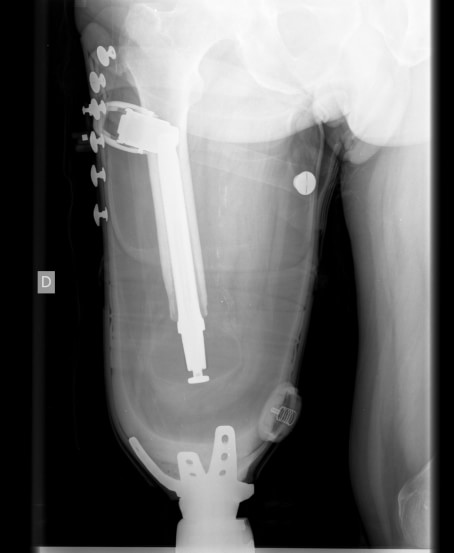

La técnica de la Endoprótesis ya se realiza en España

Jueves, 01 Agosto 2013 Categoría: Amputaciones Visitas: 9404